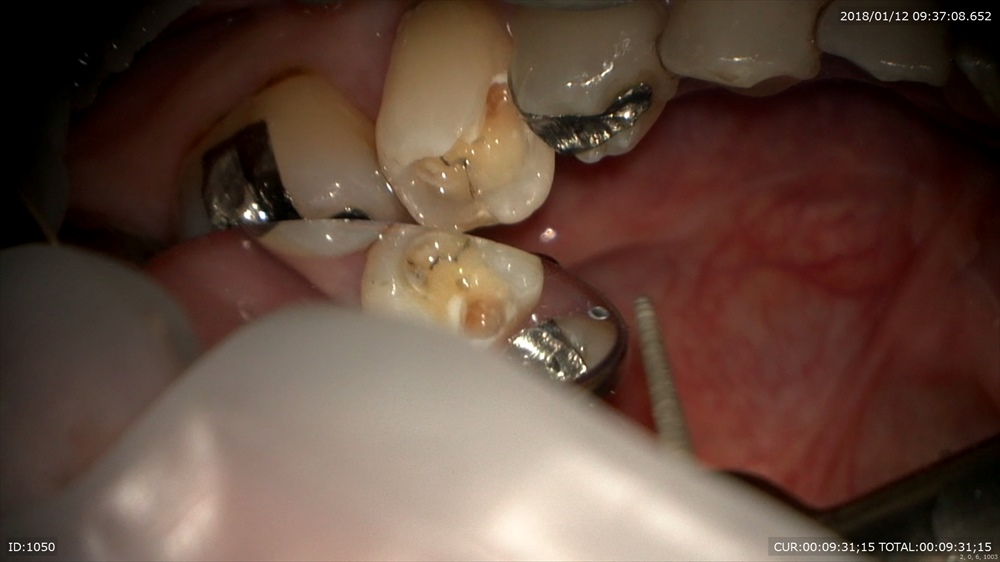

「銀歯むし歯で銀歯がとれた」

一見なにもないように見えて

このセメントの下は。ほらむし歯

感染部位を染めて

マイクロスコープで無痛治療(麻酔していません)

むし歯自体は痛みを感じないのでマイクロスコープで治療を行うとそのような恩恵もあります!

治療中痛みがあるところは知覚があるところ=健康な歯質なのです

丁寧に

次回詰め物がはいります。